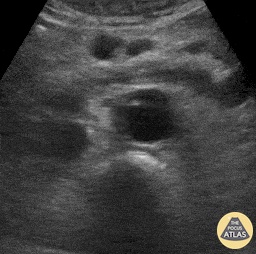

Aorta - Aortic Dissection Flap

61 year-old male presented with one day history of generalized abdominal pain, nausea, and vomiting. He was hemodynamically stable (BP 130/59); EKG notable for the presence of U waves and lateral ST depressions; labs revealed a negative troponin, potassium 3.1, lactic acid 5.4. Abdominal POCUS seen here revealed an abdominal aortic dissection flap as his unifying diagnosis. Richard Cunningham, MD. Emergency Medicine